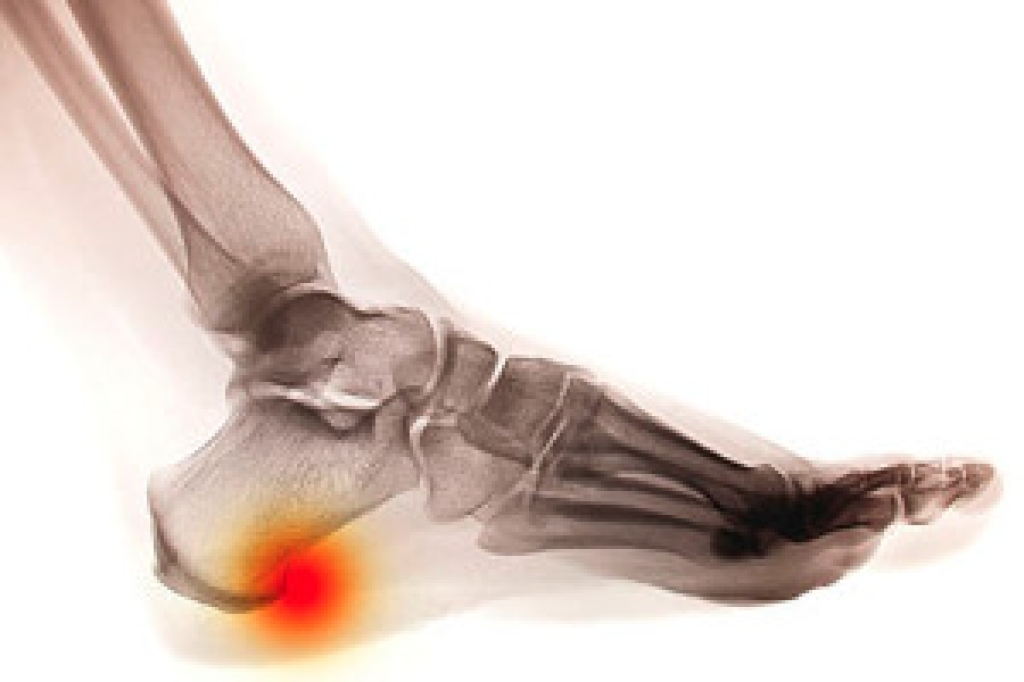

Podiatrists often perform two tests – blood tests and x-rays – when trying to diagnose bunions, especially in the early stages of development. Blood tests help determine if the foot pain is being caused by something else, such as arthritis, while x-rays provide a clear picture of your bone structure to your provider.